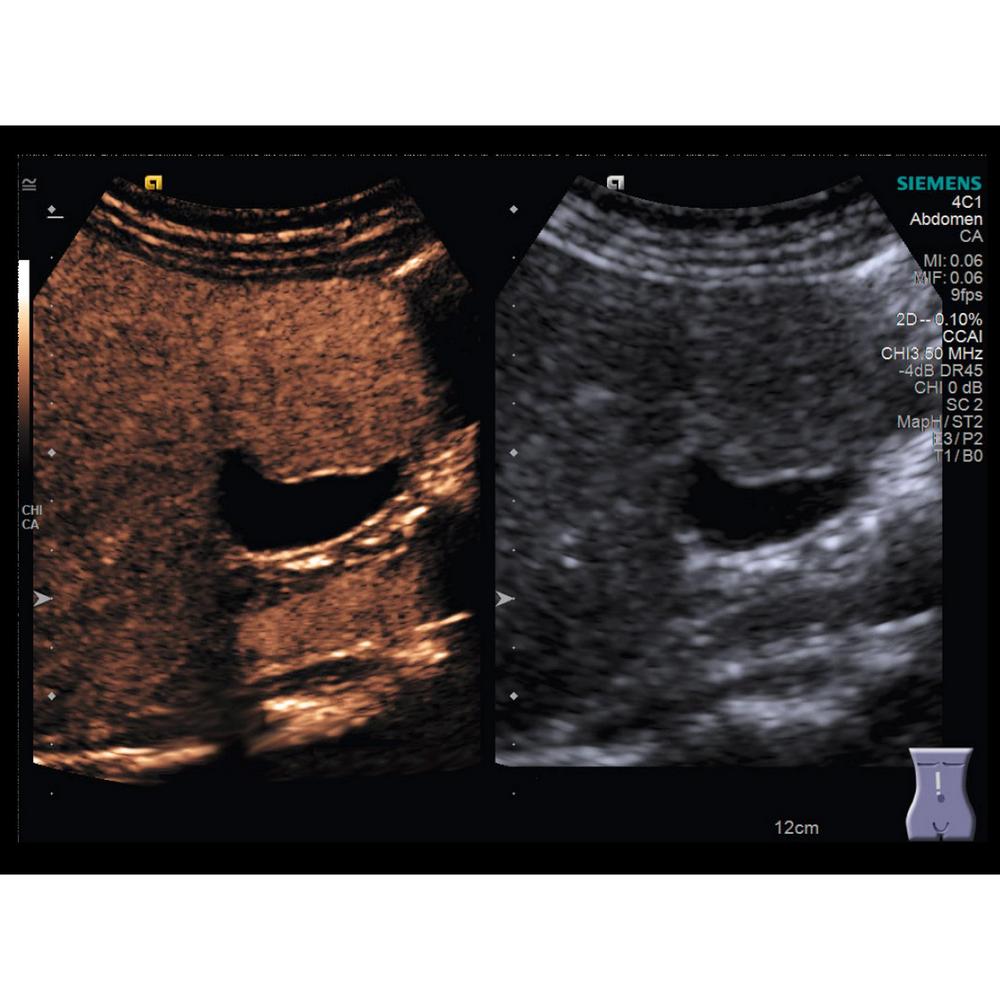

- 3D-изображения КТ и МРТ в сочетании с ультразвуковым изображением в режиме реального времени.

- Важнейшая информация о патологическом процессе, необходимая для проведения интервенционных процедур, и комплексный анализ всего массива данных.

• Визулизация высокого класса с контрастным усилением.

• CHI – технология для диагностики мельчайших и затененных областей, что важно для выявления онкологии на ранних стадиях.